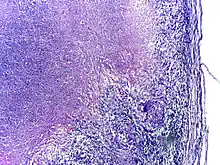

Microscopy of tuberculous epididymitis. H&E stain

Tuberculosis is classified as one of the granulomatous inflammatory diseases. Macrophages, epithelioid cells, T lymphocytes, B lymphocytes, and fibroblasts aggregate to form granulomas, with lymphocytes surrounding the infected macrophages. When other macrophages attack the infected macrophage, they fuse together to form a giant multinucleated cell in the alveolar lumen. The granuloma may prevent dissemination of the mycobacteria and provide a local environment for interaction of cells of the immune system.[63] However, more recent evidence suggests that the bacteria use the granulomas to avoid destruction by the host's immune system. Macrophages and dendritic cells in the granulomas are unable to present antigen to lymphocytes; thus the immune response is suppressed.[64] Bacteria inside the granuloma can become dormant, resulting in latent infection. Another feature of the granulomas is the development of abnormal cell death (necrosis) in the center of tubercles. To the naked eye, this has the texture of soft, white cheese and is termed caseous necrosis.[63]